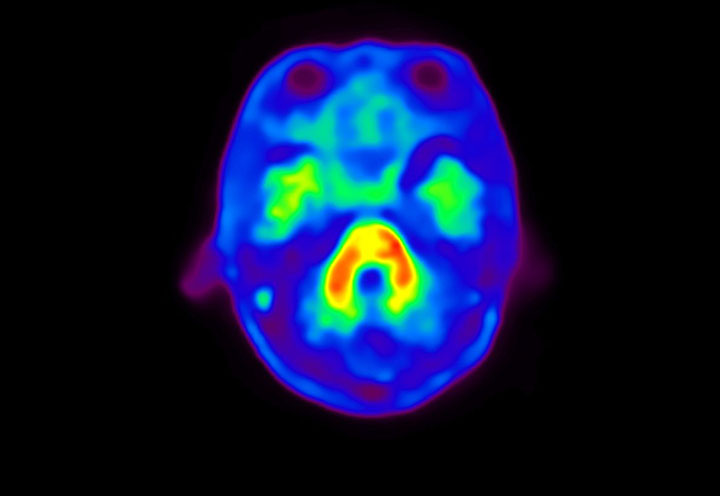

Head / Case4 : Amyloid

Coronal

Courtesy : Kindai University Hospital

- Imaging protocol

- Injected dose: 3.21 MBq/kg, 18F-Flutemetamol

- Uptake time: 100 minutes

- Scan time: 20 minutes